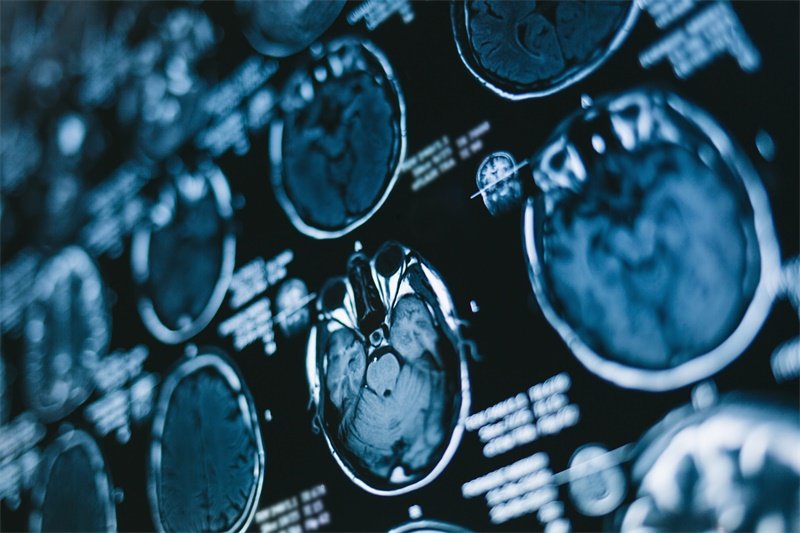

普通MRI:软组织的天下

MRI是磁共振成像,不用X射线,靠磁场和射频脉冲让身体里的氢原子产生信号,重建成图像。普通MRI最大的优势就是看软组织,分辨率比CT高很多。脑灰质白质的分界、脊髓的神经束、关节的软骨和韧带、盆腔器官的细节,核磁能看得很清楚,很多早期病变CT上看不到,核磁能发现。

而且没有电离辐射,这一点让很多人安心。但代价是慢,扫一个部位可能要二三十分钟,期间不能动。机器声音也很响,医院会给你塞耳塞。体内有心脏起搏器、某些金属植入物的人,需要先确认能不能做,不是所有金属都不行,但要提前告知医生。

脑部检查,为什么首选核磁而不是CT

其实正好相反。脑子里大部分重要的东西都是软组织:脑白质、脑灰质、小脑、海马、脑干、神经束……这些在CT上都看不清楚。CT对脑子的价值主要是急性期出血,比如突发剧烈头痛高度怀疑蛛网膜下腔出血,几分钟之内要有结果,这时候才首选CT。但如果是慢性头痛、怀疑肿瘤或者脱髓鞘病变,CT能提供的信息非常有限,换核磁才能真正看清楚。

脑瘤随访也是一样。治疗结束后,每次复查几乎都是增强核磁,看肿瘤有没有变化、有没有复发。CT在这里没什么优势,不是检查越贵越准,而是核磁确实更适合这个场景。